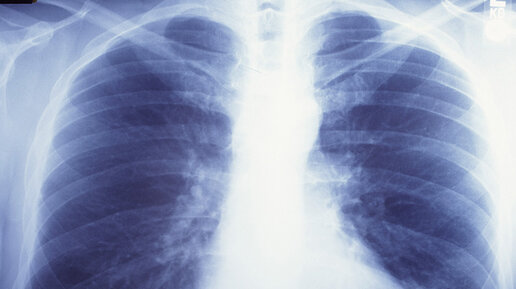

Сможет ли флюорография или рентген показать коронавирус?